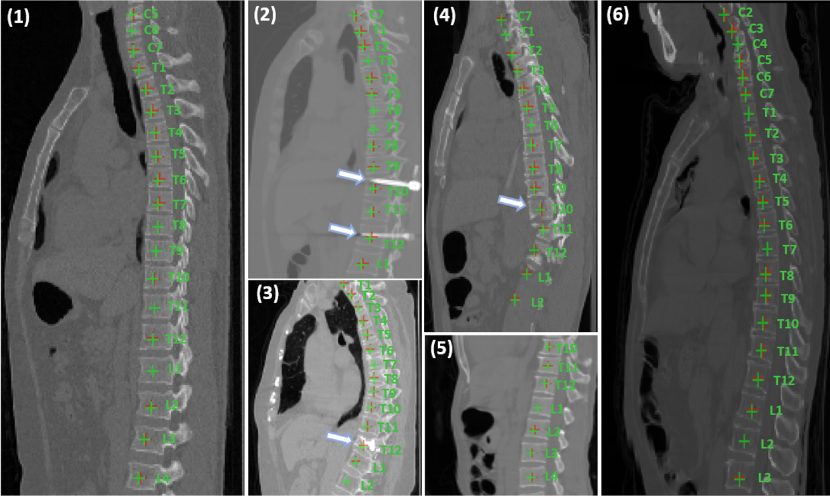

◆Multi-View Vertebra Localization and Identification from CT Images, MICCAI 2023, Vancouver, Canada, October 8-12, 2023. [Han Wu, Jiadong Zhang, Yu Fang, Zhentao Liu, Nizhuan Wang, Zhiming Cui, Dingggang Shen]

从 CT 图像中准确定位和识别椎骨对于各种临床应用至关重要。然而,大多数现有的工作都是在 3D 上进行裁剪 patch 操作,这类方法计算成本高昂并且捕捉的全局信息有限。在本文中,我们提出了一种从 CT 图像中进行多视角脊椎定位和识别的方法,将 3D 问题转化为不同视角上的 2D 定位和识别任务。我们的方法在不受三维 patch 限制的情况下可以自然地学习多视角的全局信息。此外,我们提出了一种多视角对比学习策略来预训练网络更好捕捉多视角下不变的解剖结构特征。为了更好捕捉序列信息,我们还引入了序列损失作为额外监督来维持预测椎骨中的序列结构。评估结果表明,仅通过两个 2D 网络,我们的方法可以准确地定位和识别 CT 图像中的椎骨,并且始终优于最先进的方法。